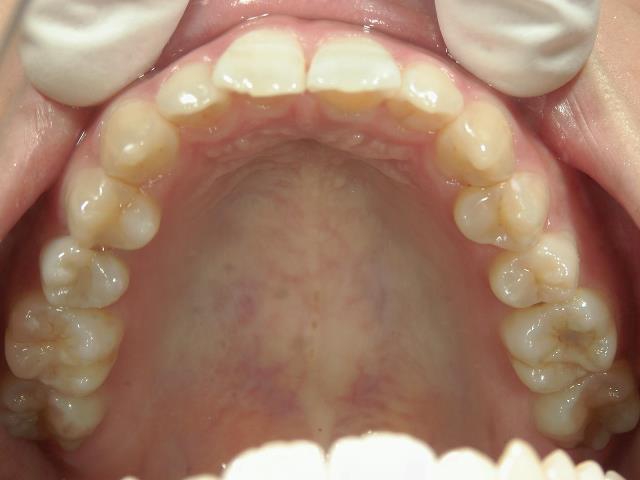

矯正歯科 治療前 上顎